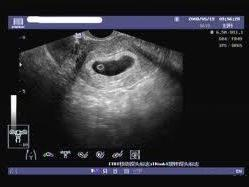

通過B超檢查發(fā)現(xiàn)胚胎未按照正常時間發(fā)育,如未按時出現(xiàn)胚芽、胎心等,可能是空孕囊的表現(xiàn)。

10、羊水過少或無羊水

羊水是胎兒生長的重要環(huán)境,如B超檢查發(fā)現(xiàn)羊水過少或無羊水,可能是空孕囊的征兆。